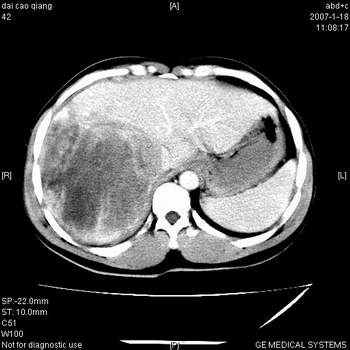

符合巨块型肝癌表现:

1、平扫低密度,增强后表现为快进快出。

2、动脉期可见迂曲的动脉供血血管

3、并可见门静脉右支癌栓形成

4、可见假包膜

5、腹主动脉旁结节影,考虑肿大淋巴结。

肝右叶巨大不均匀低密度肿块,前缘有假包膜,增强明显的呈快进快出表现,门脉右支有癌栓,病人虽然年轻但还是首先考虑肝右叶巨块形肝癌,病人血象高只能说有合并感染。不支持肝脓肿。